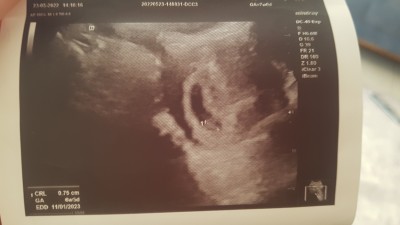

Cinsiyet tahmini ters rahim karından

Tam 7 haftalık

Kiz daha 6 haftakik neyin tahmini

Tam olarak kaçıncı haftada belli olur sizce şimdi 9 hafta 4 günlük